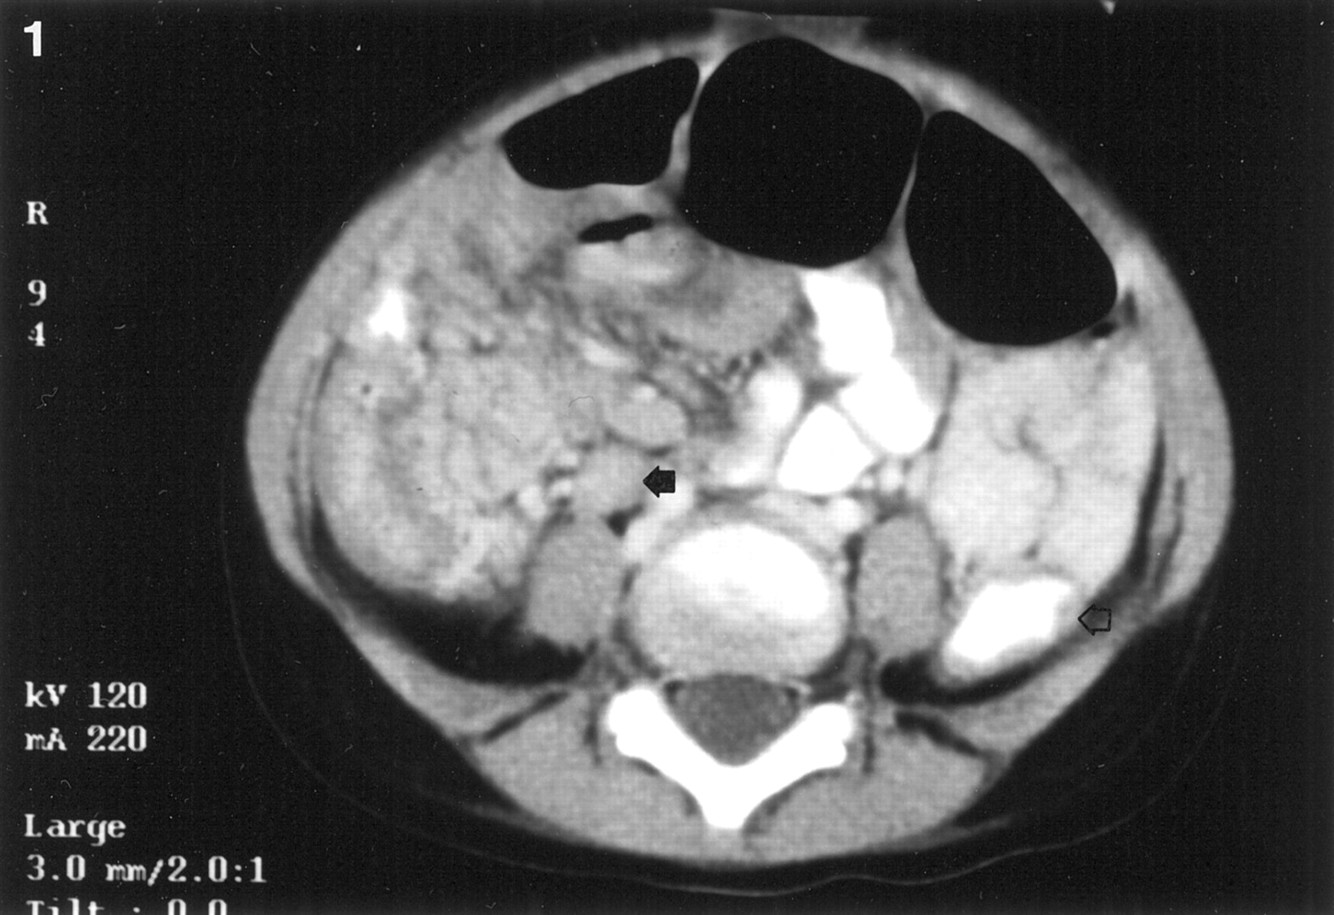

Ddx?

Bacteroides fragilis (intra-abd abscess, PID, or pulmonary infection)

Prevotella melaninogencia (pulmonary or periodontal abscess)

What would you expect to see on gram stain of the organism cultured from the finding here?

Gram - coccobacilli

(Intra-abdominal abscess = bacteroides fragilis)